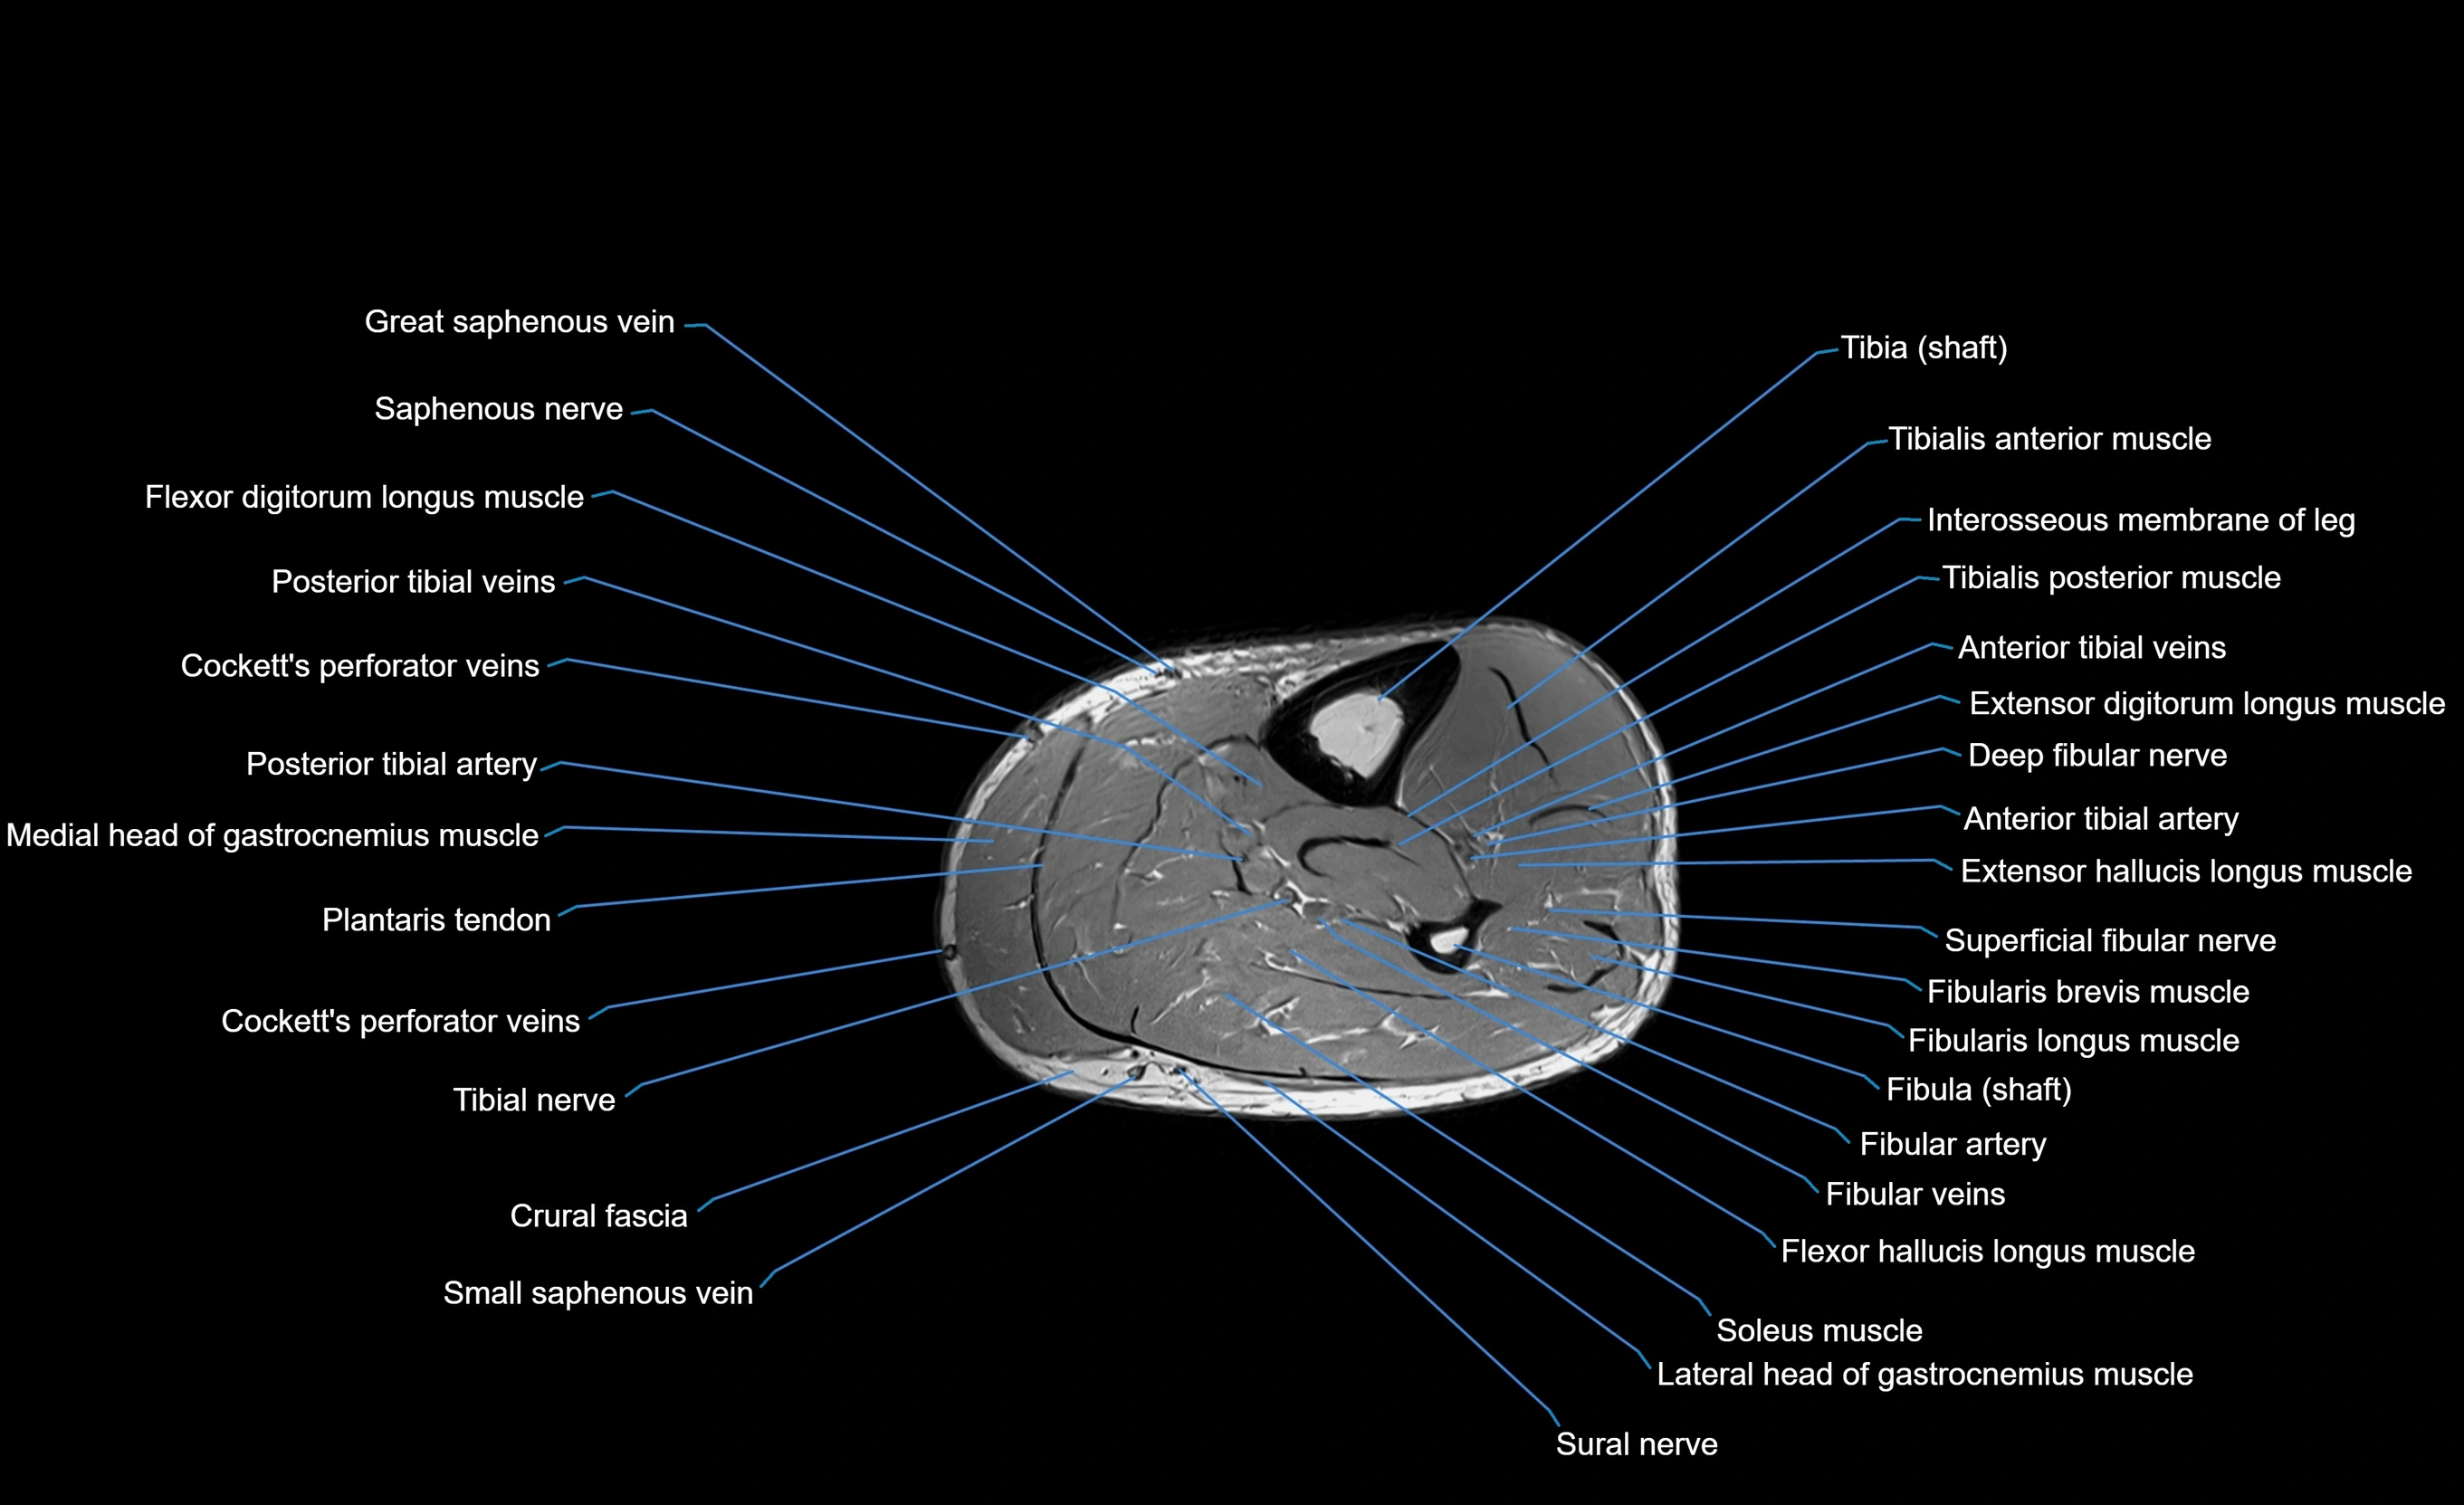

MRI image